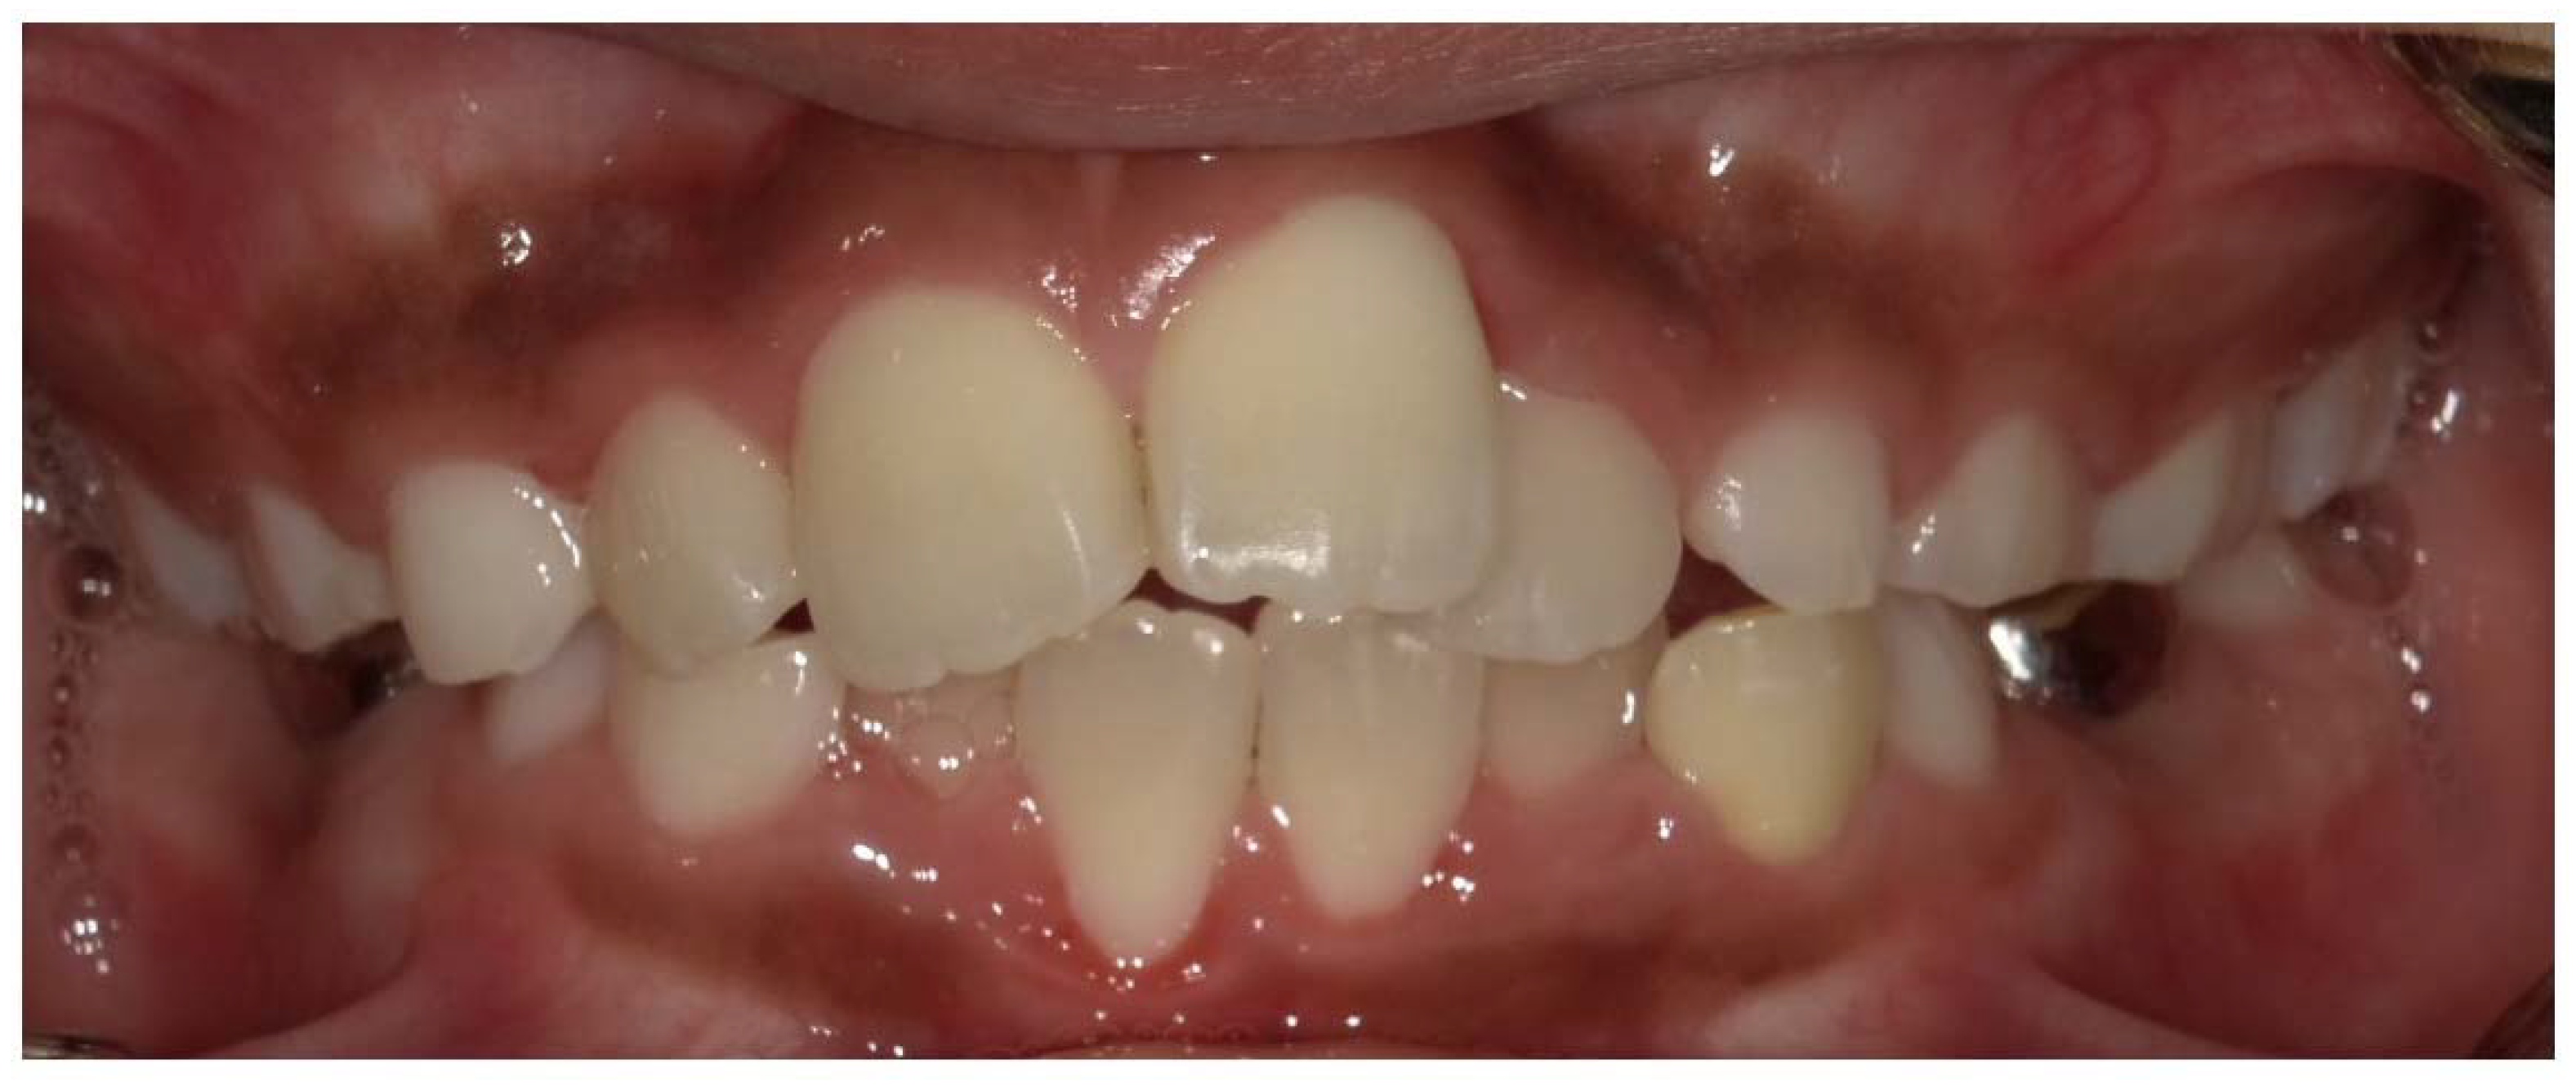

The dentin defects found in XLH patients are sometimes accompanied by a thinner layer of enamel [8], although the structure of enamel is normal [7,26]. The thin enamel tends to wear faster and expose the poorly mineralized dentin, leading to pulpal infection [7]. Additionally, delayed eruption, short roots, root resorption, a poorly defined lamina dura, and a hypoplastic alveolar ridge were recognized in a patient with XLH [7]. Whether caries activity is higher in children with XLH compared with healthy subjects is unknown; however, caries progresses easily via the thin enamel and poorly mineralized dentin [7]. Children with XLH often present with delayed dental development, abnormal eruption patterns, and increased frequency of specific malocclusions (Figure 6). An open bite or impacted or ectopic eruption of maxillary canines due to delayed maxillary growth in relation to mandibular growth has been reported [37,38,39].

Figure 6.

Crowding in the anterior region of a male X-linked hypophosphatemia (XLH) patient aged 10 years 1 month.